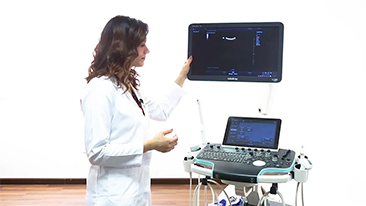

We work closely with our customers so our products and systems meet evolving clinical needs. Mindray aims to provide you with comprehensive imaging solutions for more precise diagnosis and confident treatment in different applications.

Portable, highly mobile and versatile equipment came to the fore in point-of-care (POC) particularly when wards and operating theatres are spread across several floors and access to specialist devices is at a premium.